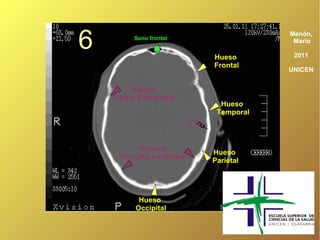

6         Seno frontal

Frontal

UNICEN

Sutura

Fronto Esfenoidal

Hueso

Temporal

Occipito parietales

Parietal

Occipital

6 Seno frontal Hueso Menón, Mario 2011 Frontal UNICEN Sutura Fronto Esfenoidal Hueso Temporal ¿? ? Suturas Hueso Occipito parietales Parietal Hueso Occipital